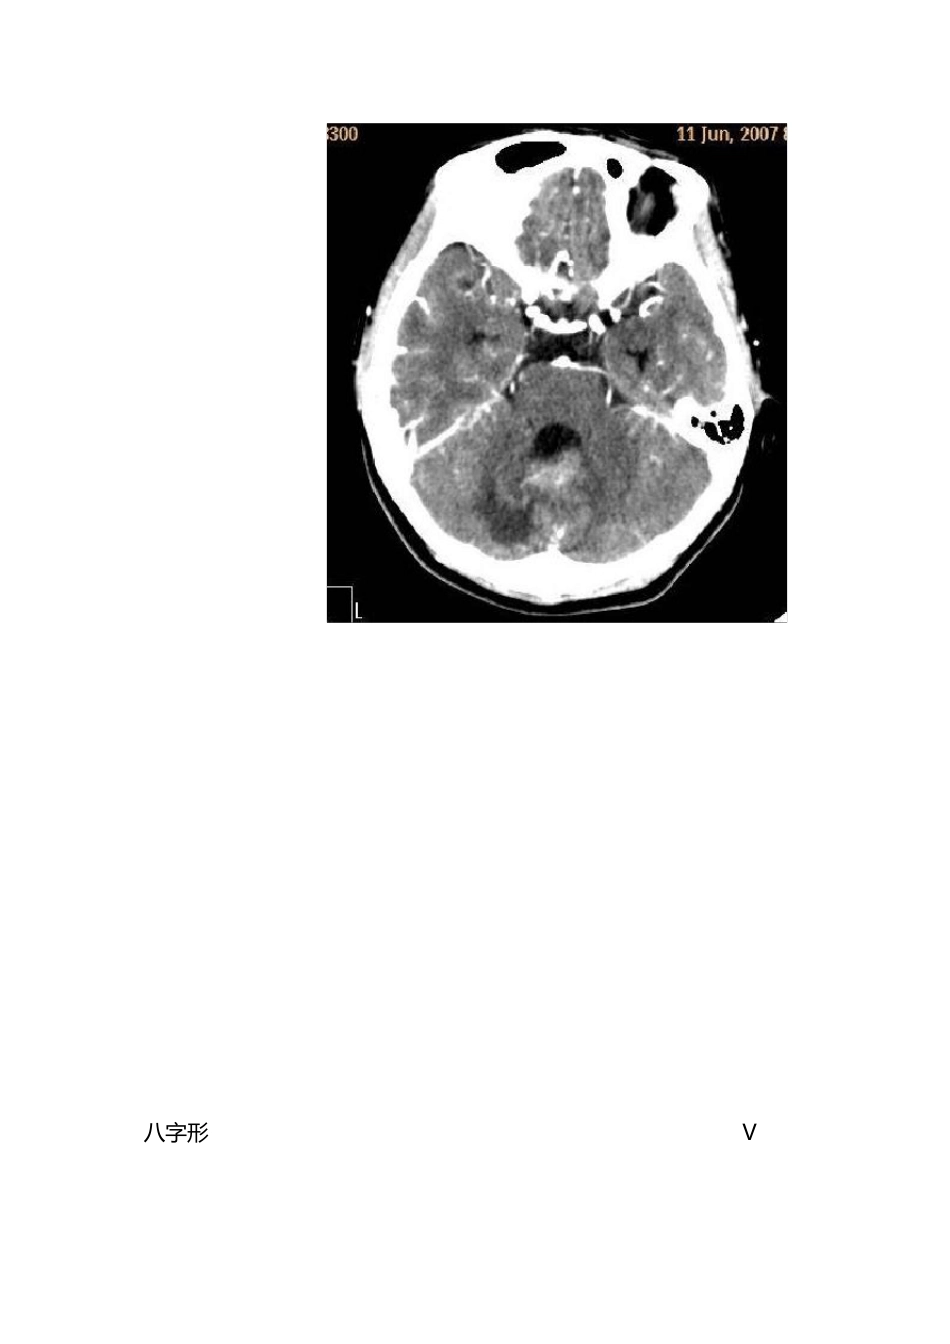

影响解剖学 知识点 学 期 结 束 了 , 在 此 把 学 的 知 识 整 理 一 下 , 这 里 有 老 师 讲 课 中 强调 的 考 试 重 点 , 也 有 以 后 到 临 床 要 注 意 的 问 题 。 这 里 不 安 书 本 的 章 节 顺序 …… 一 , 中 枢 神 经 系 统 1、颅中 窝:蝶鞍两侧从前至后 依次为眶上裂、圆孔、卵圆孔、棘孔。 (眶上裂通过动眼神 经 、滑车神 经 、三叉神 经 的 眼神 经 以 及外展神 经 , 圆孔通过上颌神 经 , 卵圆孔通过下 颌神 经 , 棘孔通过脑膜中 动脉) 2、脑干的 组成:中 脑、脑桥、延髓。 3、大脑半球比较重 要 的 三个沟:中 央沟、外侧沟、顶枕沟。 4、颅缝的 封合时间是 30—50 岁, 闭合顺 序 是矢状缝、冠状缝、人字缝。 5、鞍上池的 形状有 五边形和六边形,五边形时后 方为脑桥上缘,六边形时正后 方为脚间池,脚间池向后 通环池,四叠体池(呈“W”型)。脚间池和环池环绕的 脑组织是中 脑。 6、小脑幕的 形态: 有 八字形、V 形、Y 形 八字形 V形 Y形 Y 形 7、大脑半球从外向里的结构:脑皮质、脑髓质、基底核、第三脑室 8、 大脑大动脉环(基底动脉环):由前交通动脉、双侧大脑前动脉起始部、两侧颈内动脉、两侧后交通动脉及两侧的大脑后动脉起始部构成,又称 Willis 环. 二、头颈部 9、中耳的结构:包括鼓膜、咽鼓管、鼓室、听小骨、乳突窦,乳突小房。 10、内耳从前内到后外结构为:耳蜗、前庭、半规管 11、面神经管的分段:内耳上段、鼓室内壁段、乳突段 12、常见变异:鼓室盖低位、乙状窦前位、导静脉高位 13、窦口鼻道复合体(OMC):即前组副鼻窦在中鼻道开口区域,包括(上颌窦口、)钩突、筛漏斗、半月裂、筛泡、中鼻甲和中鼻道. 14、硬脑膜窦: 三、消化系统 15、食管的三个狭窄、三个压迹的名称 三 个 狭 窄 : 第 一 狭 窄 : 位 于 食 管 与 咽 的 连 接 处 , 距中 切 牙 15cm。 第 二 狭 窄 : 位 于 食 管 与 左 支 气 管 交 叉 处 , 距 中切 牙 25cm。 第 三 狭 窄 : 位 于 食 管 穿 膈 肌 处 ( 通 过 食 管 裂 孔处 ) , T10 水 平 , 距 中 切 牙 40cm。 三 个 压 迹 : 主 动 脉 弓 压 迹 、左 主 支 气 管 压 迹 、左 心房压 迹 ( 最长最浅)...